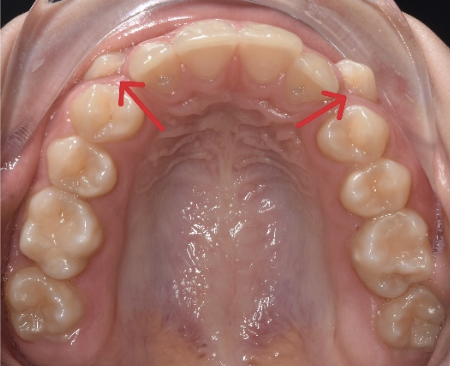

Aici avem un caz in care inghesuirea dentare grava s-a rezolvat prin tratament orthodontic cu extractii dentare.

Se poate observa ca nu exista spatiu pentru eruptia caninilor.